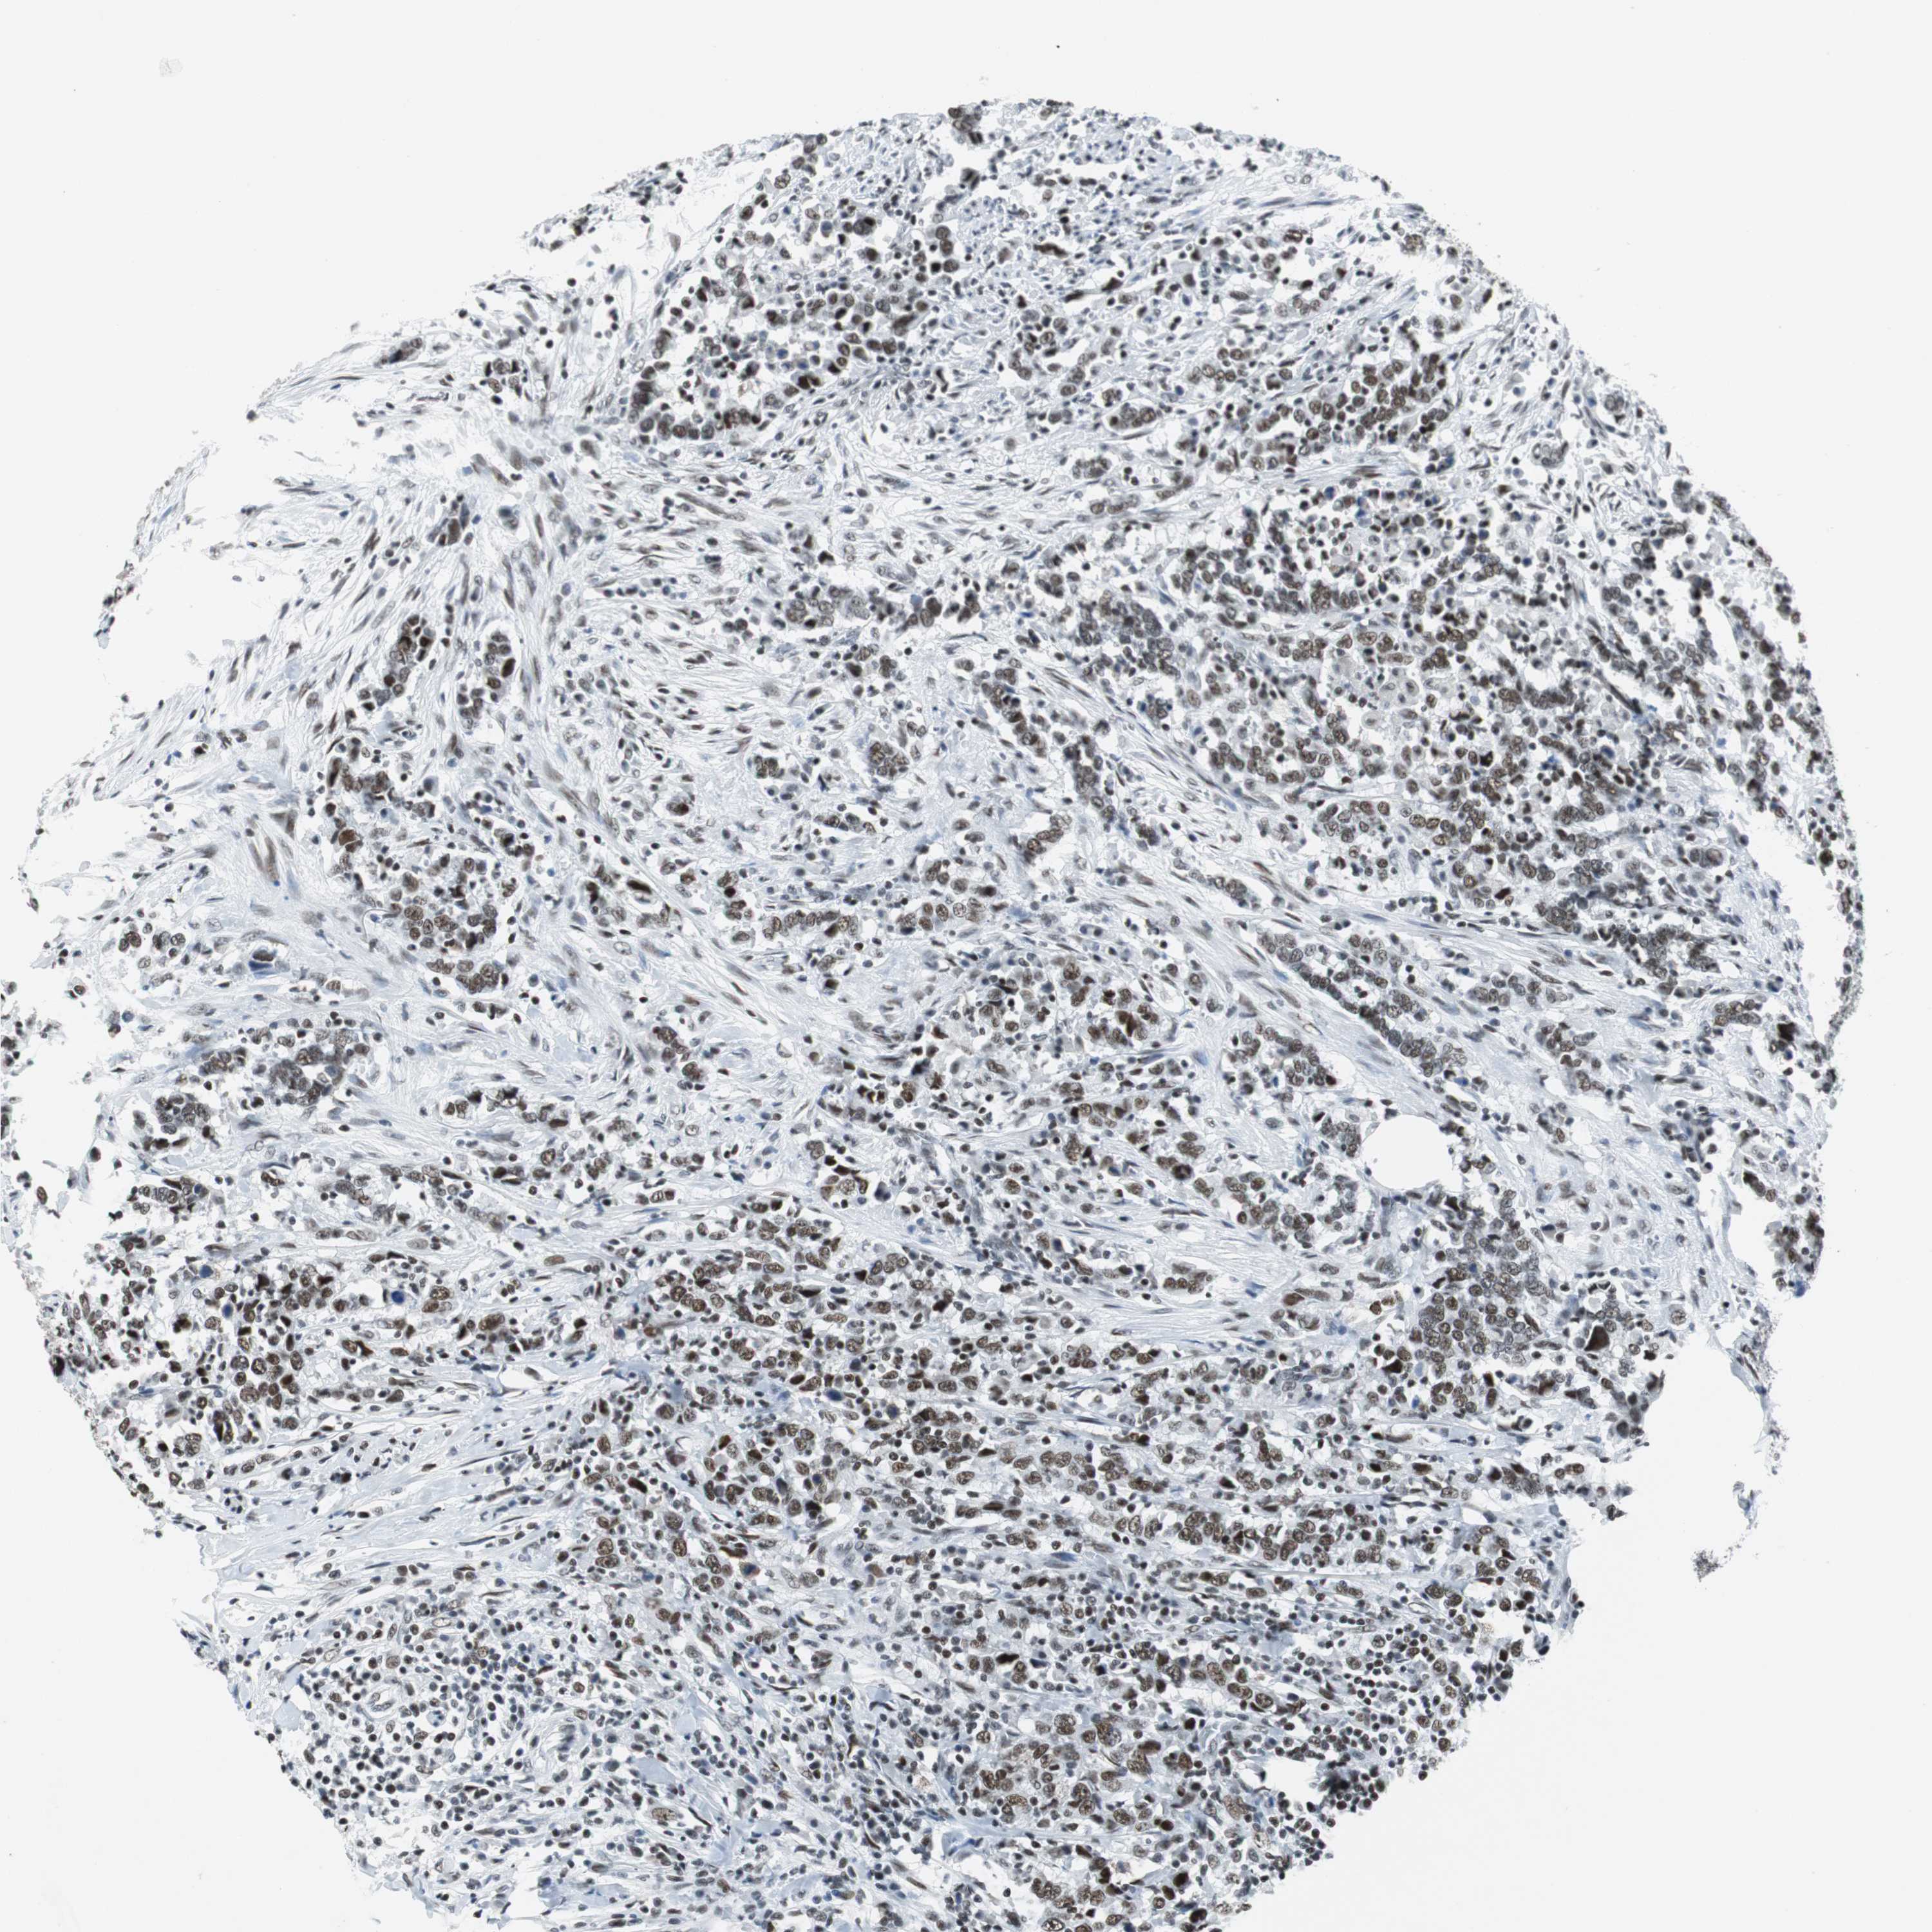

UROTHELIAL CANCER - Protein expressioni

A mouse-over function shows sample information and annotation data. Click on an image to view it in a full screen mode. Samples can be filtered based on level of antibody staining by selecting one or several of the following categories: high, medium, low and not detected. The assay and annotation is described here.

Antibody stainingi

Antibody staining in the annotated cell types in the current human tissue is reported as not detected, low, medium, or high, based on conventional immunohistochemistry profiling in selected tissues. This score is based on the combination of the staining intensity and fraction of stained cells.

Each image is clickable and will lead to virtual microscopy that enables deeper exploration of all samples and also displays staining intensity scores, fraction scores and subcellular localization as well as patient and tissue information for each sample.

Antibody HPA052052

Urothelial carcinoma, High grade